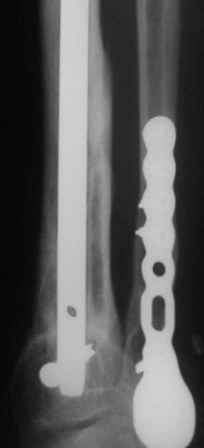

А я бы хотел еще раз подчеркнуть ключевую роль вмешательства на малоберцовой кости в подобной ситуации. В приведенном примере при открытом переломе произошла потеря большого фрагмента большеберцовой кости. Фиксация интрамедуллярным гвоздем с одним блокирующим винтом проксимально и одним дистально. Плюс стабильный остеосинтез малоберцовой. Консолидация за три месяца без костной пластики в условиях ранней нагрузки.